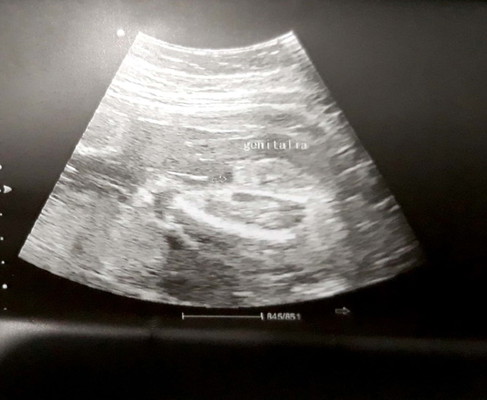

BOY OR GIRL?

Hello po! Gusto ko lang po makahingi ng ibang opinyon, yung nag ultrasound kasi sakin parang madaling madali. Wala din sya nilagay sa result namin kung ano talaga gender ni baby. Ano po kaya sa tingin nyo? Sabi nya kasi habang nag uusap kami baby boy daw. Malabo din po ang kuha sa ultrasound, eto na po ang best angle. Thank you mommies!